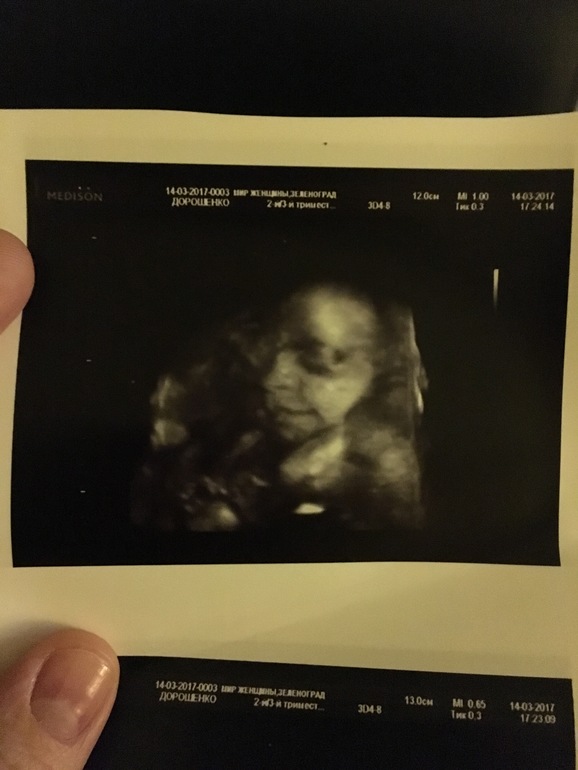

Ну и моя горошинка (3 д УЗИ ,26 неделек нам здесь )

Понимаю вашу радость! Мы тоже ждём девочку! И очень рады, так что словами не передать!!! Малышка такая прикольная улыбается на 3д! И мамочка хорошенькая!!!

Спасибо !! Очень приятно ! Я за Вас тоже очень рада ! Это счастье ожидать чудо такое ! А малышка моя да ,улыбалась мне все время на УЗИ )